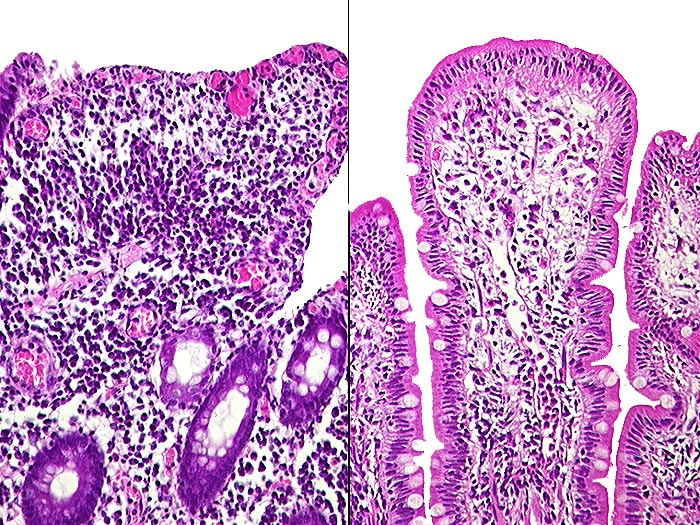

PathoPic ID 409 - Florider Morbus Crohn

Florider Morbus Crohn

Entzündung / Reparatur

Ileum

Darm, Anus

Beide Bilder stammen aus derselben Biopsie der Dünndarmanastomose. Rechts praktisch normale Dünndarmschleimhaut. Links verplumte oberflächlich erodierte Zotten.

St.n. Ileozökalresektion vor 20 Jahren wegen Morbus Crohn. Rezidivierter Dünndarmileus.

Histologie